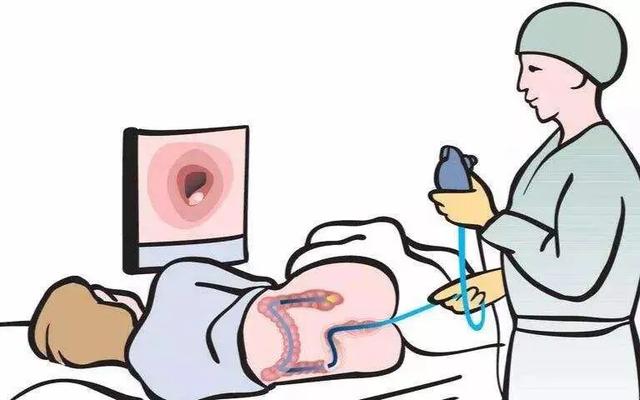

クリニックで胃内視鏡検査をしていると、家族の一人に胃がんが見つかり、家族全員で胃内視鏡検査のために人間ドックに来た、こんな場面に出くわした。私の友人で、一緒に遊ぶ仲間がいて、よくタバコを吸い、一緒にお酒を飲み、夜遅くまでスナック菓子を食べ、とても楽しくて幸せだったのですが、その中の一人が便に血が混じっていたので、大腸がんを見つけるために大腸内視鏡検査をしに来たのですが、その時、一緒に遊ぶ仲間が、よくタバコを吸い、一緒にお酒を飲み、夜遅くまでスナック菓子を食べ、夜遅くまで起きているので、怖くて怖くて、その結果、一緒に遊ぶ仲間全員が胃内視鏡検査に1ヶ月間並ぶことになったのですが、もちろん何の問題もないのですが、せめて、みんなが安心して、一日中怖がらなくてもいいように検査するためです。一日中怯えている必要はない。幸い、結果は大した問題ではない。

現在、消化管腫瘍は臨床における全腫瘍の半数以上を占めており、早期食道がんや消化管がんは胃内視鏡検査でしか発見できず、超音波検査、CT、MRIなどの他の検査では早期消化管がんや食道がんを発見できないため、定期総合検診では胃内視鏡検査も行う必要がある。

2.胃镜

超音波検査では、胃の中のガスが医師の判断を妨げるため、胃をはっきりと見ることはできません。CTで見る場合は、主に胃の外側の粘膜を見ることになる。この時、医師が直視で胃の内壁を見ることができる胃カメラが作られた。

胃の増殖は胃カメラではっきり見ることができる。そして、その腫瘤組織を少し病理部に持って行き、生検をすることで、胃がんかどうかを判断することができます。胃がんであれば、胃カメラとCTの結果によって、早期胃がんなのか、中・後期胃がんなのか、臨床病期が導き出され、その後の治療の指針となる。

2、胃がん、食道がんが最も恐れられている胃カメラ。

胃のむかつきがあり、胃に問題があると思われる場合、超音波検査、画像診断、フィルム検査は胃カメラ検査には及びません。なぜなら、私たちの消化管は空洞だからです。箱の中に何があるのか知りたい時、一番いい方法は箱を開けることですが、箱を開けることは私たちの体に手術をするようなもので、費用が高すぎます。ケースの外側が腐っていれば、がんは手術のチャンスを失っている。胃カメラ検診は、年齢が40歳以上で、次のいずれかに該当する人に勧められる:

(2)胃がんの初期症状は、一般的な胃炎や胃潰瘍の症状と明らかな違いはなく、胃痛や上腹部不快感だけであったり、まったく症状がなかったりする。胃がんを発見する最も直接的で正確な方法は、胃カメラ検査である。胃カメラは、前面にハイビジョンカメラが付いたチューブを口から挿入して胃まで送り、胃の中を見ることができます。

三、消化内镜

- 胃内視鏡検査には胃カメラと大腸カメラがあり、胃がん、大腸がん、腸がん、食道がんを発見することができる。

食道がん、胃がん、十二指腸がん、大腸がんの検診最も直接的で効果的な方法は、胃カメラと大腸カメラである。病変の位置、大きさ、形状を明確にすることができ、さらに重要なことは、生検で病理検査を行うことで病気の性質を明らかにすることである。例えば、腺癌の分化度(高分化型、中分化型、低分化型、刷り込み細胞癌の順に悪性度が高くなる)を明らかにすることができる。しかし、時には特殊なケースもある。例えば、生検で腫瘍が一度に拾い上げられなかったり、多くは慢性炎症を報告する。この場合、胃に癌はなく、確かに胃炎や粘膜潰瘍である場合と、癌はあるが、付随する炎症や潰瘍が邪魔をして結果が出ない場合、あるいは生検で粘膜の炎症部分しかとれず、深い部分の癌細胞がとれなかった場合がある。そして、内視鏡医が病変が疑わしいと判断すれば、2~3週間、経口酸抑制薬(オメプラゾールやパントプラゾールなどのプロトンポンプ阻害薬)を内服するように患者にアドバイスし、その後、再度、胃カメラ検査と生検を行います。この場合、必ず医師のアドバイスに耳を傾け、薬を服用し、再度生検を行うことをお勧めします。